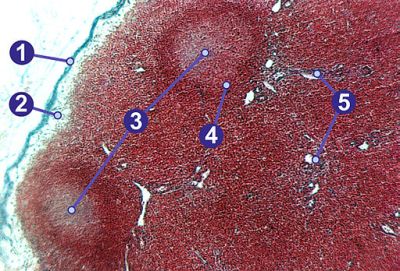

Lymph node (labels) – histology slide

Lymph node, showing (1) capsule, (2) subcapsular sinus, (3) germinal centers, (4) lymphoid nodule, (5) trabeculae. (Description text from the Wikimedia Commons file page.)